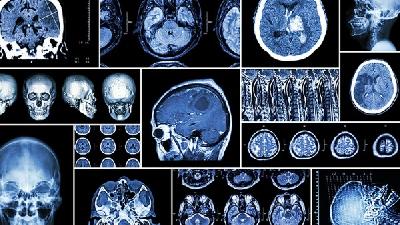

脑瘫儿童可通过康复训练、药物治疗、手术治疗、辅助器具等方式治疗。脑瘫通常由产前脑发育异常、围产期缺氧缺血、产后脑...

脑瘫可能由产前缺氧、早产低体重、新生儿黄疸、遗传代谢异常等原因引起,症状表现为运动障碍、肌张力异常等,需通过康复...

脑瘫病无法完全治愈,但可通过康复训练、药物治疗、手术治疗、辅助器具等方式改善功能。脑瘫是由非进行性脑损伤导致的运...